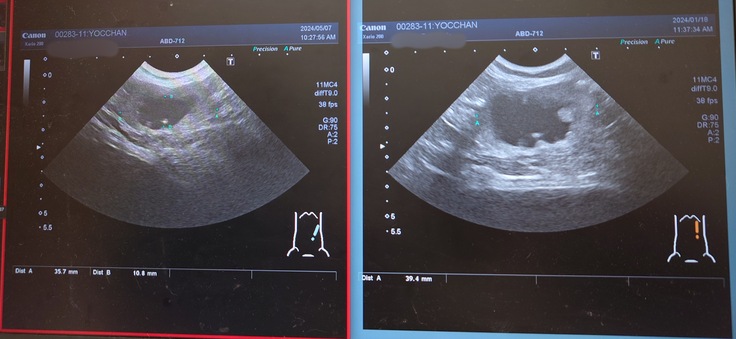

ヨッちゃんのエコー検査の結果です。

正常な右の腎臓腎盂。

画像の右側が前回のエコーで、左側が今回のエコー。

腎盂が肥大している左の腎臓。

左側の拡大していた尿管。

左側の腎盂は相変わらず肥大したままでエコーが黒く写っていました。

腎臓のサイズは右側の腎臓が45.8mmから42.1mm、左側の腎臓が39.4mmから35.7mmになっていて、前回よりも腎臓の大きさが縮小していて、もしかしたら腎臓の機能が低下しているのかもしれないということでした。ヨッちゃんの症状は良くなることはないという覚悟は頭の片隅に置いてるつもりですが、やっぱり聞くと毎回ガビーンとなります😨

でも、尿管拡張していて腎盂腎臓が肥大している左側の尿管が2.1mmから1.1mmに細くなっていてこれは良い結果だったので安心しました😊